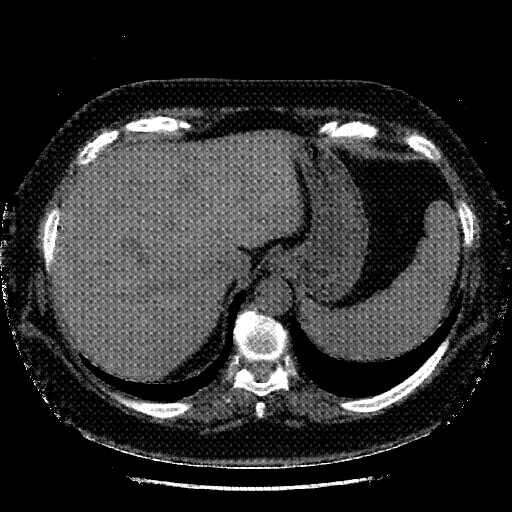

Generated VENOUS CT scan (A→B translation)

No window - Raw intensity values

Lung window (WL -600, WW 1500 β†’ Low βˆ’1350, High +150)

Mediastinum window (WL 40, WW 400 β†’ Low βˆ’160, High +240)